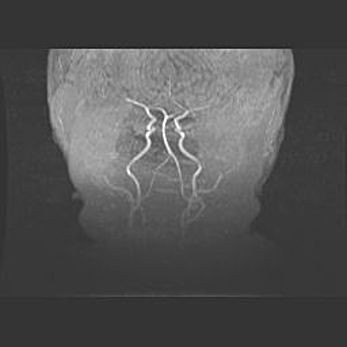

Церебральная ишемия II.

Возраст: 7 дней

Вес: 3350 г

Пол: женский

Окружность головы: 35 см

Срок гестации: 39 недель

Ишемия головного мозга – это состояние, которое развивается в ответ на кислородное голодание вследствие недостаточного мозгового кровообращения. У новорожденных она является следствием дефицита кислорода, что ведет к метаболическим расстройствам различной степени тяжести в тканях головного мозга, в том числе к развитию коагуляционных некрозов и гибели нейронов.